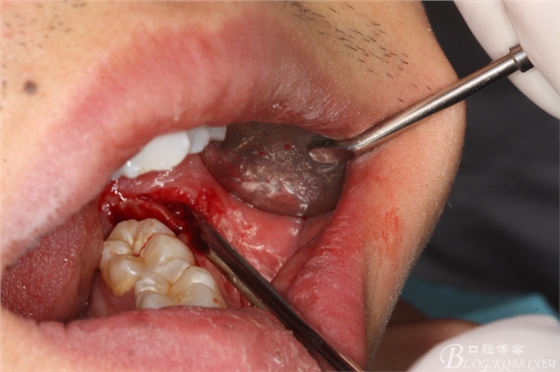

圖7.頰側(cè)潛掘法完成頰側(cè)牙冠橫斷

圖8.潛掘法橫斷牙冠后。繼續(xù)把牙冠近遠(yuǎn)中截?cái)?,即所謂的”T"型分牙